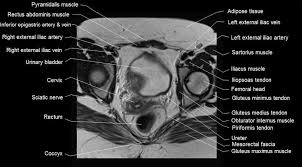

The muscles of the pelvis form its floor. This mri male pelvis axial cross sectional anatomy tool is absolutely free to use. Anatomical drawing of the female pelvis. The floor is composed of two muscular layers, the levator ani/coccygeus complex and. • to assess equivocal imaging findings • staging of hepatic neoplasms • metastatic workup of primary malignancies • diagnosis of abdominal masses • assessment of biliary problems • diagnosis of vascular lesions.

Axial pelvis ct axial femur ct axial femur ct axial knee ct. The muscles of the pelvis, hip and buttock anatomical chart shows how each muscle in this area of the body works with the others, and the various minor systems within the major ones. Hepatocellular carcinoma or liver cancer. The floor is composed of two muscular layers, the levator ani/coccygeus complex and. There are many muscles that form the pelvic floor, including puborectalis, pubococcygeus, iliococcygeus and coccygeus. Pelvic floor muscles that are located wholly within the pelvis. Almost every movement in the body is the outcome of muscle contraction. The muscles are connected with the bones. Learn about anatomy muscles pelvis with free interactive flashcards. The gastrocnemius muscle is a complex muscle that is fundamental for walking and posture. Attached to the bones of the skeletal system are about 700 named. Muscles, connected to bones or internal organs and blood vessels, are in charge for movement. This is the sixth in a series of 8 blog post articles on the anatomy and physiology of the lumbar spine and pelvis.

Ct Abdomen And Pelvis Coronal Anatomy In The Male Cute766 from i0.wp.com Ct anatomy of the pelvis. N patient preparation n patient position n scanogram. organs and structures of the female pelvis. The pelvic girdle consists of two symmetrical halves. The muscles are connected with the bones. The muscular system is responsible for the movement of the human body. They support the pelvic organs especially during increases in intra abdominal pressure and also aid in urinary and faecal. The lateral superficial muscles, the transversus and external and internal oblique muscles, originate on the rib cage and on the pelvis (iliac crest and inguinal ligament) and are attached to the anterior and posterior layers of the sheath of the rectus.

Ct anatomy of the pelvis. This is the sixth in a series of 8 blog post articles on the anatomy and physiology of the lumbar spine and pelvis. Although ultrasound is frequently indicated for the primary. This article reviews the anatomical and functional information of the gastrocnemius muscle, its embryological derivation. Pelvic girdle and floor female pelvis and reproductive organs male pelvis and reproductive organs urinary bladder and urethra perineum nerves pelvic organ prolapse kegel exercises. To support the abdominal and pelvic viscera. The direct (straight) head and indirect (reflected) head. N patient preparation n patient position n scanogram. Their main function is contractibility. We study anatomy at the practical anatomy class we study the human body. Use the mouse scroll wheel to move the images up and down alternatively use the tiny arrows (>>) on both side of the image to move the images. Abdominal and pelvic anatomy encompasses the anatomy of all structures of the abdominal and pelvic cavities. Hint you are sitting on it right now.

Radiological Anatomy X Ray Ct Mri Kenhub from thumbor.kenhub.com Their main function is contractibility. Axial pelvis ct axial femur ct axial femur ct axial knee ct. Ct anatomy of the pelvis. This mri male pelvis axial cross sectional anatomy tool is absolutely free to use. Rib thorax lumbar pelvis sacrum coccyx femur fibula tibia. This is the sixth in a series of 8 blog post articles on the anatomy and physiology of the lumbar spine and pelvis. The muscles of the pelvis form its floor. Included within the chart are gorgeous illustrations of the pelvic diaphragm, sphincter muscles, gluteus maximus.